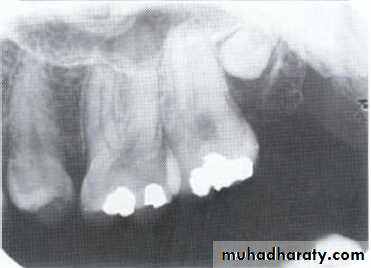

Microdontia.

Macrodontia.Size

Microdontia:

(1) True Generalized Microdontia.

(2) Relative Generalized Microdontia.(3) Focal or Localized Microdontia.

All teeth are smaller than

normal.Occur in some cases of

pituitary dawrfism.

Exceedingly rare.

Teeth are well formed.

(1) True Generalized Microdontia

Normal or slightly smaller than normal teeth.

Are present in jaws that are somewhat larger than normal.(2) Relative Generalized Microdontia

(3) Focal/Localized MicrodontiaCommon condition.

Affects most often maxillary

lateral incisior + 3rd molar.

These 2 teeth are most often

congenitally missing.

sides converge or taper

together incisallyforms cone-shaped crown

root is frequently shorter

than usual.

(3) Focal/Localized Microdontia